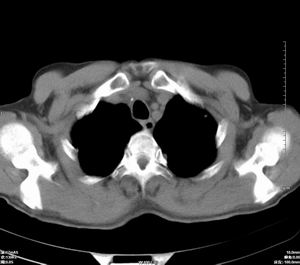

男 60岁,咳嗽,胸疼半年,请各位老师讨论.

肺内多发小结节,部分内见空泡,边界大部分清楚.多考虑:1 韦格氏肉芽肿.2 肺泡癌伴肺内转移不除外.

肺内多发结节样病灶,部分内见空泡影,边界大部分清楚,多考虑:

1.金葡菌感染

2 转移不除外

影像学表现:文献报告肺部浸润性见于50-65%的病人,肺部均有浸润,表现为肺内多发或单发结节影,出现多发厚壁空洞,内壁粗糙,易合并细菌性肺炎,也可出现胸腔积液。ct及hrct扫描可见大小不等的结节多分布于肺周边部,结节可呈楔形贴近胸膜,另一主要特征是其周围有线状斑痕影,即长毛刺征,受累血管及血管周围纤维化是其形成的原因,如累及胸膜尚可出现胸膜凹陷征。71%ct比胸片发现更多更小病灶, 典型的征象滋养血管征仅能在ct上显示。ct及hrct可检出典型影像征象。为诊断提供了重要依据,ct可成为肺韦格氏肉芽肿首选检查方法。